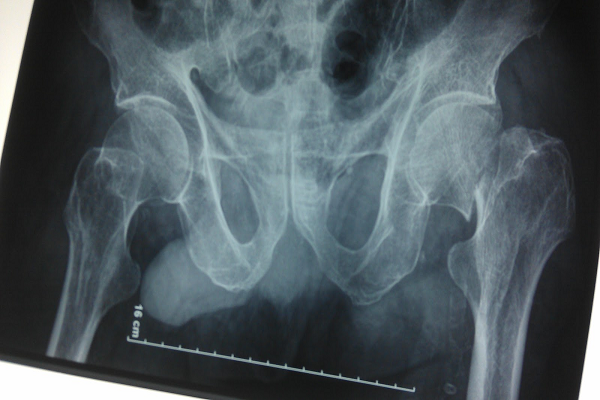

Gãy cổ xương đùi là tình trạng Gãy xương đùi ở gần khớp hông. Khớp hông là một khớp dạng cầu, là điểm giao nhau của xương chậu và xương đùi. Gãy cổ xương đùi tức là gãy phần cổ xương gần với khớp hông, nằm ngay dưới chỏm xương đùi. Nguồn máu cung cấp đến chỗ gãy xương thường bị gián đoạn, vì vậy chỗ gãy này khó lành. Tuy nhiên hầu hết mọi người phục hồi hoàn toàn sau khi phẫu thuật.

Bác sĩ tiến hành chẩn đoán bằng cách khám tổng quát để xác định bệnh. Trong một số trường hợp nếu các triệu chứng không rõ ràng hoặc dễ nhầm lẫn với loại bệnh khác, bác sĩ sẽ yêu cầu chụp X-quang cổ xương đùi. Phim X-quang sẽ xác định vị trí gãy chính xác và mức nghiêm trọng của vết gãy.